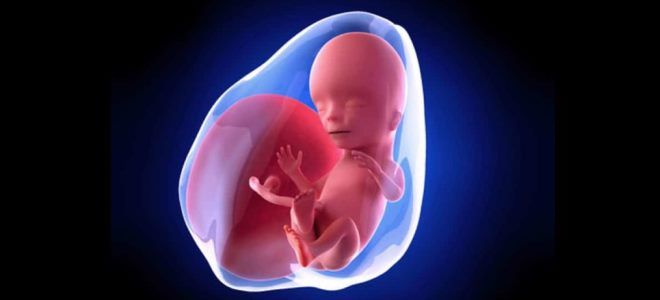

Как выглядит плод на 15 неделе?

На 15-й неделе беременности внешний вид плода претерпевает изменения. Пропорции различных частей тела начинают выравниваться: ножки становятся длиннее ручек и уже не отстают в росте. Ушные раковины к этому моменту полностью формируются и выглядят почти как у взрослых, только в уменьшенном размере. Из-за сближения глазниц также меняются черты лица. Тем не менее, малыш все еще не напоминает маленького ребенка: 15 недель — это еще ранний срок, и его внешность не окончательно сформирована.

На поверхности кожи начинают появляться пушковые волоски. Они тонкие, короткие и практически незаметные. Основная их задача — поддержание стабильной температуры тела и участие в терморегуляции. Кожа плода все еще имеет красноватый оттенок, но уже не так прозрачна, как раньше. Активность плода возрастает, и вскоре беременная женщина сможет ощутить его первые движения. Однако на 15-й неделе плод еще не обладает достаточной силой, чтобы мама могла четко почувствовать его шевеления.

Беременность 15 недель – развитие плода

На 15-й неделе беременности развитие плода характеризуется активным ростом головного мозга. Начинают формироваться первые извилины, которые выглядят как небольшие бороздки. Нервные клетки продолжают активно делиться, что способствует увеличению объема мозга. Постепенно он начинает координировать движения, которые выполняет малыш.